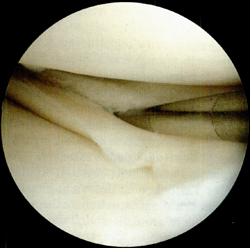

Типовий розрив меніска з вивихом типу «ручка лійки» на схемі і через артроскоп

Якщо такі епізоди повторюються, виникає необхідність в операції з видалення розірваної частини меніска. Це нескладна і безпечна операція, яку виконують через проколи шкіри під контролем артроскопа - тонкого оптоволоконного зонда діаметром близько 0,5 см, до якого приєднані відеокамера і джерело світла.

Під контролем відеозображення на моніторі відірвану частину меніска відсікають і видаляють.